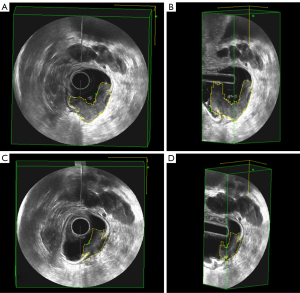

3D-ERUS was conducted 1 week before CRT (3D-ERUS1) and before surgery (6–8 weeks after completion of CRT, 3D-ERUS2) with a Pro Focus 2202 scanner (BK, Denmark) equipped with a three-dimensional (3D) endorectal probe 8838 or 2502 (6–16 MHz, BK, Denmark). The patient was placed in the left lateral decubitus position, then 50 mL gel was injected into the rectum and anal canal to expand the rectal lumen. The probe was inserted through rectum and anal canal, and advanced above the lesion of interest in order to evaluate the entire lesion comprehensively. After initial observation of the tumor, 3D volume images were obtained in all patients before and after CRT treatment by using automatic rotating imaging of sampling function, and the data was stored on the machine. 3D-ERUS volumetry measurements were performed on 3D Viewer (version 5.19, BK, Denmark) by an independent sonographer with 3 years’ experience in 3D-ERUS who was blinded to the pathology results. The lesion boundaries on the 3D-ERUS image were manually traced by the sonographer on every transverse‑sectional tumor area by a slice section thickness of 2 mm (Figure 1). After multiplying every transverse-sectional tumor area, the total volumes of the tumor were automatically calculated. The tumor volume measured pre-CRT was recorded as Vpre-CRT, whereas the tumor volume measured post-CRT was recorded as Vpost-CRT. Finally, the TVRR was calculated as TVRR = (Vpre-CRT − Vpost-CRT)/Vpre-CRT × 100% (17).

Qualitative assessment of T-restaging by 3D-ERUS

The comparisons of the 3D-ERUS and pathological results in the T-restaging of patients are shown in Table 2. T-restaging after CRT by 3D-ERUS was correct in only 20/54 (37%) patients. Overstaging occurred in 26/54 (48%) patients, while understaging occurred in 8/54 (15%) patients. There were 16 patients who met the criteria of pCR (staged as ypT0N0 or achieved TRG 0). Only 4 of these 16 patients were proven to be true positive by preoperative 3D-ERUS assessment. 3D-ERUS showed false-positive findings in 3 patients. Overstaging occurred in 12 pCR patients by 3D-ERUS (Figure 2). Qualitative 3D-ERUS assessment of rectal wall penetration showed a sensitivity of 25.00% and specificity of 92.11% in identifying T0 stage, with an accuracy of 72.22%. The area under the ROC curve (AUC) for the qualitative prediction of T0 stage was 0.586 (95% CI: 0.410, 0.761).